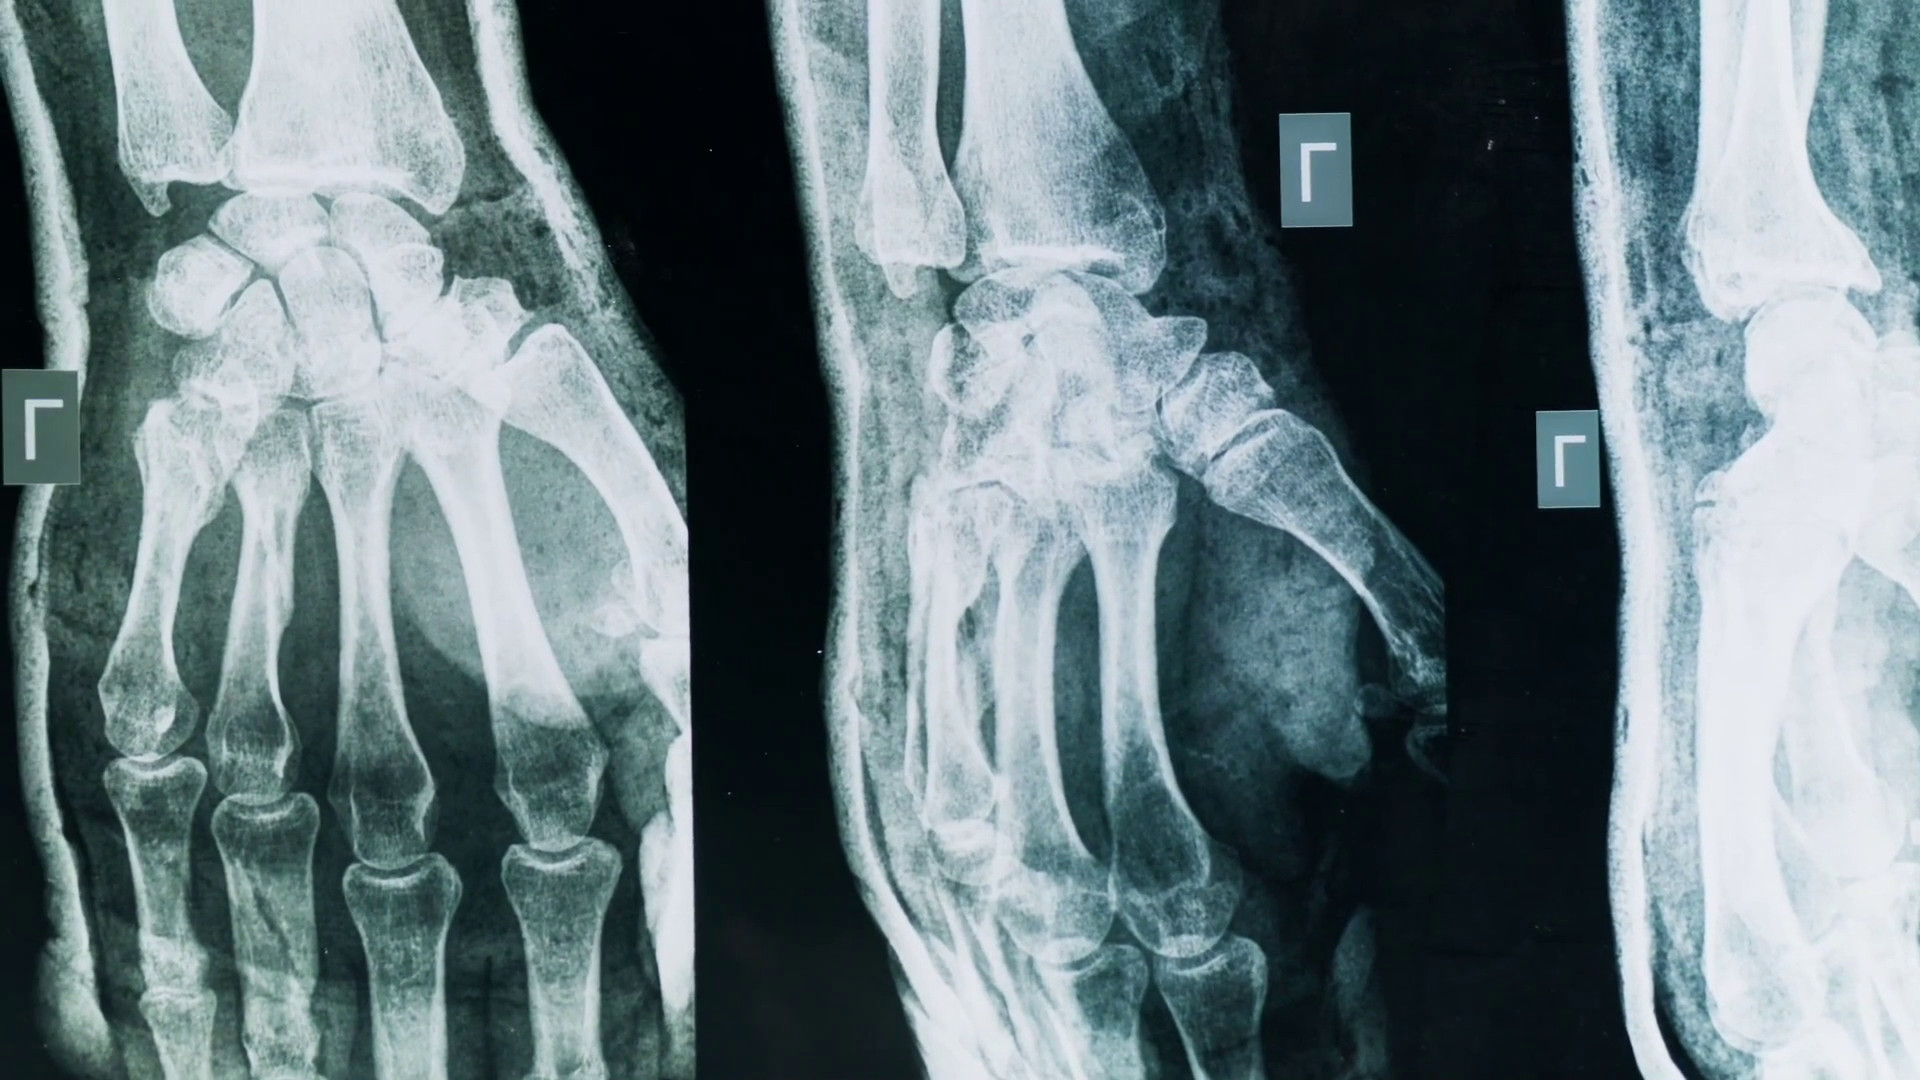

Artrite e artrosi, come riconoscerle e curarle